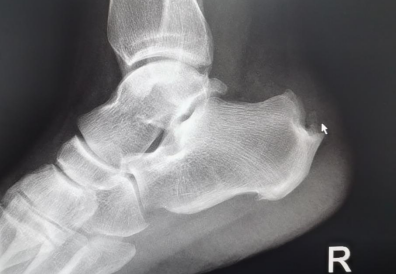

“經X光、磁共振等詳細檢查,提示患者雙側跟骨結節(jié)增生、跟腱有變性,雙側跟骨結節(jié)區(qū)域及跟腱止點表現:組織充血、水腫,結合病情及查體,考慮跟骨骨性突起畸形,經診斷,為Haglund綜合癥(止點性跟腱炎、跟骨后上突增生與跟腱滑囊炎的統(tǒng)稱)?!崩畋蛑魅伪硎荆摬“Y主要表現為跟腱止點部位疼痛不適,運動時疼痛加劇;或者清晨起床后出現疼痛,漸進性病程發(fā)展,后期疼痛加重,影響生活質量。